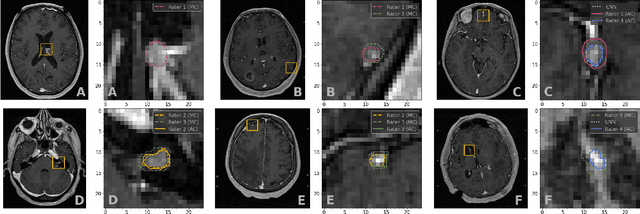

Abstract:Stereotactic radiosurgery is a minimally-invasive treatment option for a large number of patients with intracranial tumors. As part of the therapy treatment, accurate delineation of brain tumors is of great importance. However, slice-by-slice manual segmentation on T1c MRI could be time-consuming (especially for multiple metastases) and subjective (especially for meningiomas). In our work, we compared several deep convolutional networks architectures and training procedures and evaluated the best model in a radiation therapy department for three types of brain tumors: meningiomas, schwannomas and multiple brain metastases. The developed semiautomatic segmentation system accelerates the contouring process by 2.2 times on average and increases inter-rater agreement from 92% to 96.5%.